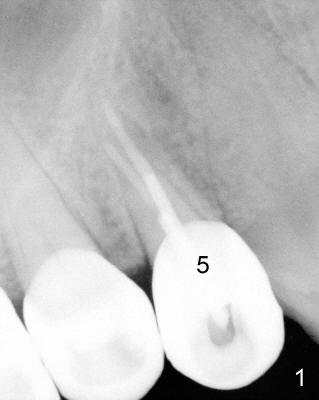

A 68-year-old male patient presented to office in March 2011 with chief complaint "upper right tooth is not comfortable". Clinical exam shows missing teeth: #13,14,30, and 31, replaced by removable partial dentures. The tooth #5 has mild mobility and percussion. Pocket depth is within normal limit. X-ray shows no significant finding (Fig.1,2). Three months later, he returned with chief complaint "The tooth has swelling". It appears that there is exostosis on buccal aspect of upper teeth. There is no erythema or tenderness on buccal mucosa around the tooth #5). But X-ray shows periradicular radiolucency (arrowheads in Fig.3,4). Cone Beam CT was recommended to confirm diagnosis of root fracture. Approximately one month later, abscess developed with fistula formation. Symptoms were controlled by taking Amoxicillin. On August 2, 2011, the patient returned for prophylaxis. The fistula was present (arrowhead in Fig.5). Gutta percha #30 was inserted into the fistula. PA was taken. The point of the gutta percha (blue arrowhead in Fig.6) points to enlarged periradicular radiolucency (black arrowheads). Deep pockets were in distobuccal and lingual. Decision was made to extract the tooth. Fig.7 shows the socket immediately extraction. The buccal plate is perforated. The septum (*) is not intact. Cracking sounds were heard during extraction. In fact the lingual root is obliquely fractured with exposed post (Fig.8: *). There is another cracking line from the buccal root to the lingual one (arrowhead). In brief, the earliest sign of root fracture is nonspecific. It should alert us to its suspicion.